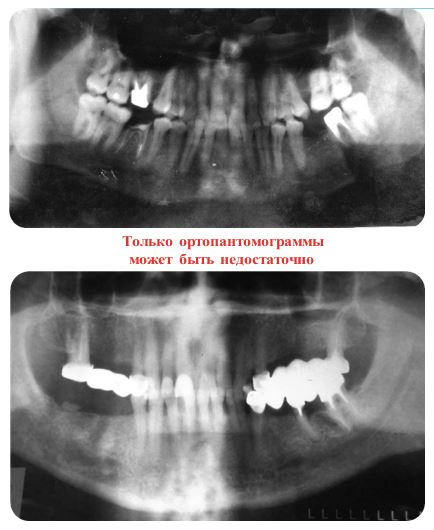

Фото 1, 2: обзорный снимок (ортопантомограмма) — объем информации для планирования имплантации ограничен, возможно оценить с определенной долей погрешности только один параметр — высоту и ориентировочно расположение некоторых анатомических образований или симптомов заболеваний, для первичной консультации данное исследование будет нужным

После исключения общих противопоказаний к установке имплантатов проводится рентгенологическое исследование. Минимально необходима обзорная рентгенография (ортопантомограмма фото 1, 2), и ее, как правило, оценивает врач при первичной консультации, но наилучший вариант – это компьютерная томография. При проведении последней врач имеет возможность оценить не только объем имеющейся костной ткани в трех плоскостях, но   также и ее структуру, что в свою очередь позволит подобрать оптимальные размер, форму, количество имплантатов и определиться с методикой операции (фото 3-4). Мой учитель по имплантологическому разделу стоматологии сказал: «Если раньше я искал показания для установки имплантатов и проводил три десятка операций в неделю, то теперь я ищу противопоказания, оперирую реже, но с более прогнозируемым результатом». Во время повторной консультации врач рассказывает о том, как все будет происходить, какие понадобятся дополнительные компоненты при установке имплантатов и почему, как